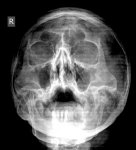

IMG20251209105704.jpg

Где пиздецома?

Синусит?+ искривление носовой перегородки

Аноним 09/12/25 Втр 12:17:36 #240 №327481316

>>327481303

Гайморит тут чот похужела от 05.12

Аноним 09/12/25 Втр 12:26:10 #243 №327481575

А как с настроением у тебя дела, не замечал изменений в последние пару недель? Нет такой, знаешь, типа необычной для тебя активности, чтр вот прямо все успеваешь, такой продуктивный и с этого сам в ахуе с себя? Или, может, наоборот - все хуйня, ничего не радует? Какой лвл кстати?

>>327481541

Сравни правую пазуху с прошлым снимком. Горизонтальный уровень видишь?

Аноним 09/12/25 Втр 12:31:36 #246 №327481750

IMG20251209143044.jpg

Желтым пазуха, красным жижка. Обвел тебе как мог у меня лапки!